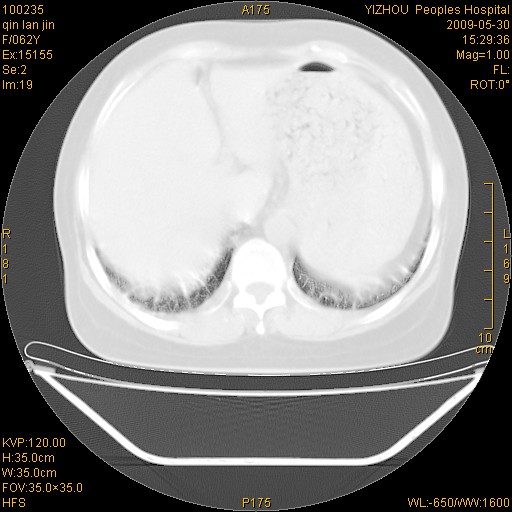

标题: CT20268:肺泡癌?间质性肺炎? [打印本页]

标题: CT20268:肺泡癌?间质性肺炎?

女,62岁,近二年经常咳嗽,近二个月,消瘦、乏力。

前面一张胸片是今天照的,后面一张胸片是去年9月份的。

弥漫性双肺间质纤维化。

两肺弥漫性间质性病变(间质性肺炎伴肺间质纤维化?)。

间质性肺炎伴肺间质纤维化。

纵隔淋巴结大,须排外癌性淋巴管炎